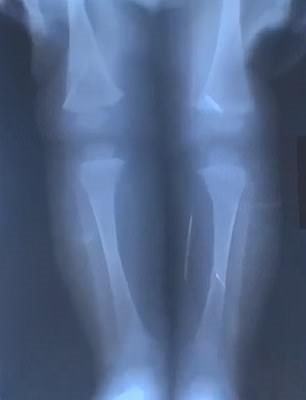

Ο μικρούλης νοσηλεύτηκε το προηγούμενο καλοκαίρι όταν ένας συγγενής ανακάλυψε μια βελόνα μέσα στο στόμα του. Το εννιά μηνών υπεβλήθη σε ακτίνες και εντοπίστηκαν 10 βελόνες.

Οι γιατροί προχώρησαν σε αρκετές επεμβάσεις προκειμένου να αφαιρέσουν τα μεταλλικά αντικείμενα από το βρέφος, που έφερε βελόνες σε κρανίο, μύτη, λαιμό, στήθος και πόδια. Όπως ανέφερε νοσοκομειακή πηγή, κάποιες από τις βελόνες είχαν σκουριάσει μέσα στο κορμάκι του όπου βρίσκονταν για περισσότερους από 3 μήνες. Αμέσως μετά το περιστατικό η μητέρα τέθηκε υπό κράτηση και παραδέχθηκε τις πράξεις της αποκαλύπτοντας και τον λόγο.